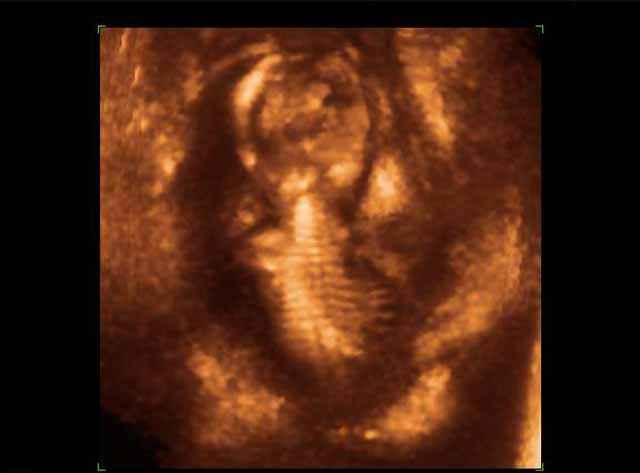

- Fetal Skeleton Ultrasound Photos

3D Ultrasound Scan Photos of Fetal Skeleton | Dr N Layyous